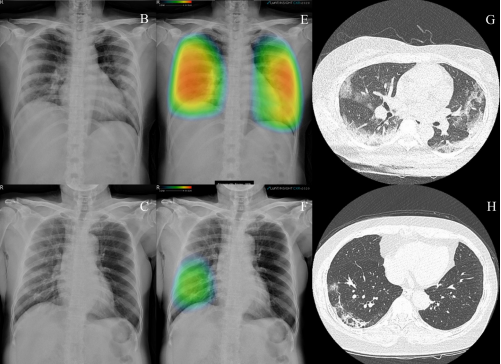

- 의료 영상 분석기(MIA) 프로젝트는 PyTorch 및 OpenCV를 활용하여 흉부 방사선 촬영(CR) 영상을 분석하여 의료 진단 및 치료 계획을 향상시키는 데 중점을 둡니다

- 현재 개발 중인 모델은 레이블링된 데이터를 기반으로 CXR 이미지에서 침윤, 폐렴 및 고착을 감지

- COVID-19 환자의 흉부 X선 이미지 및 임상 소견을 포함하는 BIMCV-COVID19+ 데이터셋 사용

- 관련 연구 논문의 인사이트를 활용하여 의료 영상에서 AI 시스템의 잠재력을 강조